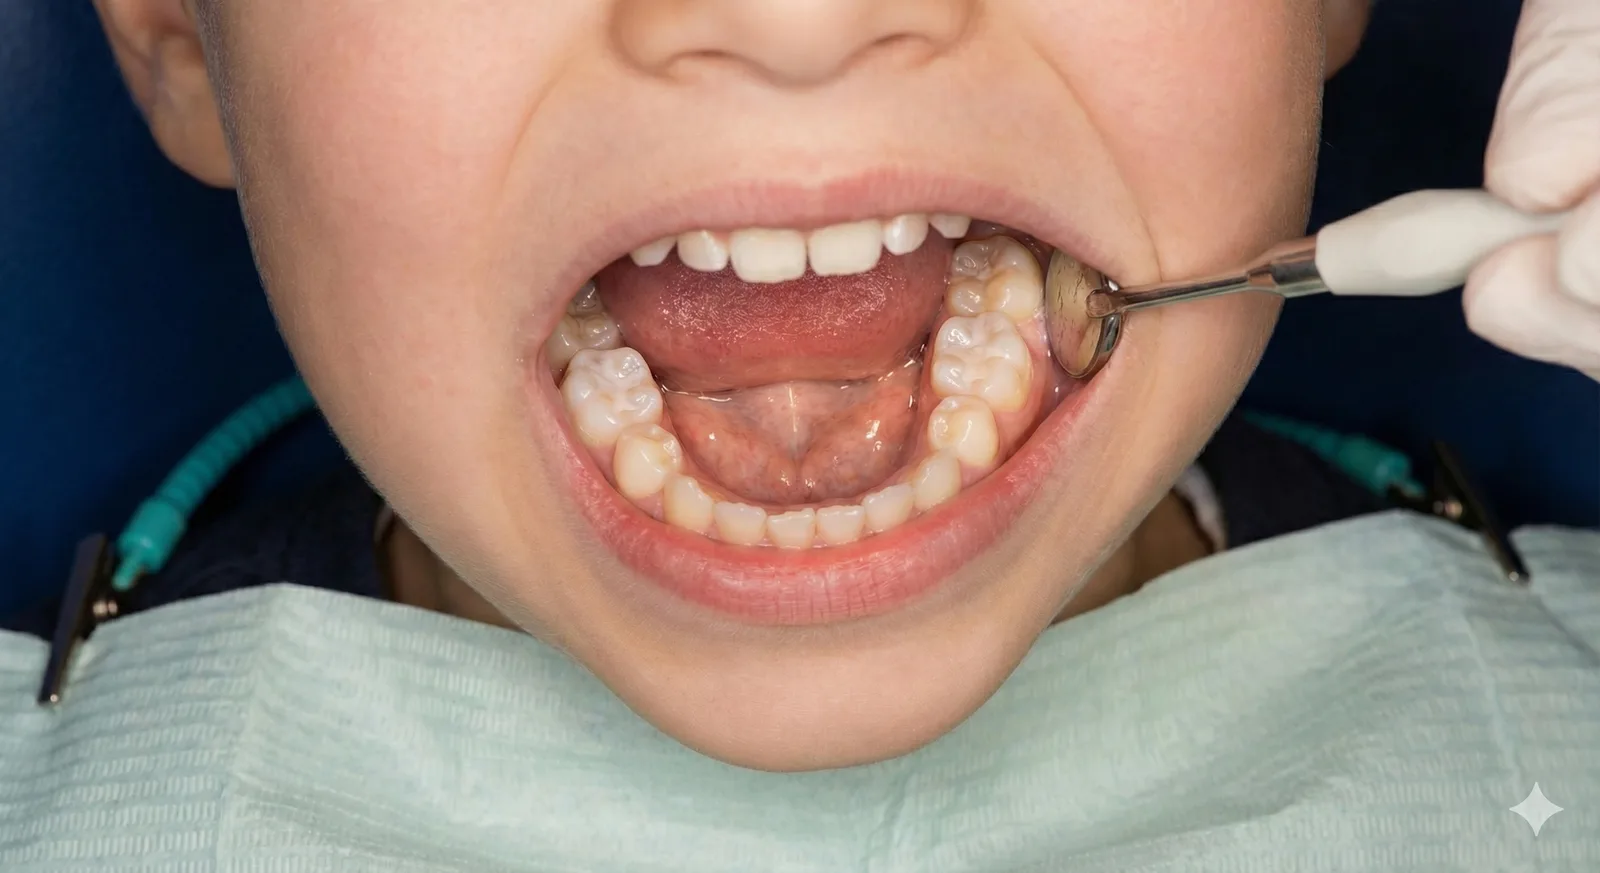

어린이의 치아는 성인보다 법랑질이 얇고 충치 진행이 빠른 편입니다. 또한 구강 구조가 성장 변화 중이기 때문에 정기적인 검진을 통해 변화 상황을 세심하게 살피는 것이 필요합니다.

유치 상태, 영구치와의 교환 상태, 교합 변화 등을 성장 단계에 맞춰 평가하고 필요한 관리 방법을 안내합니다.